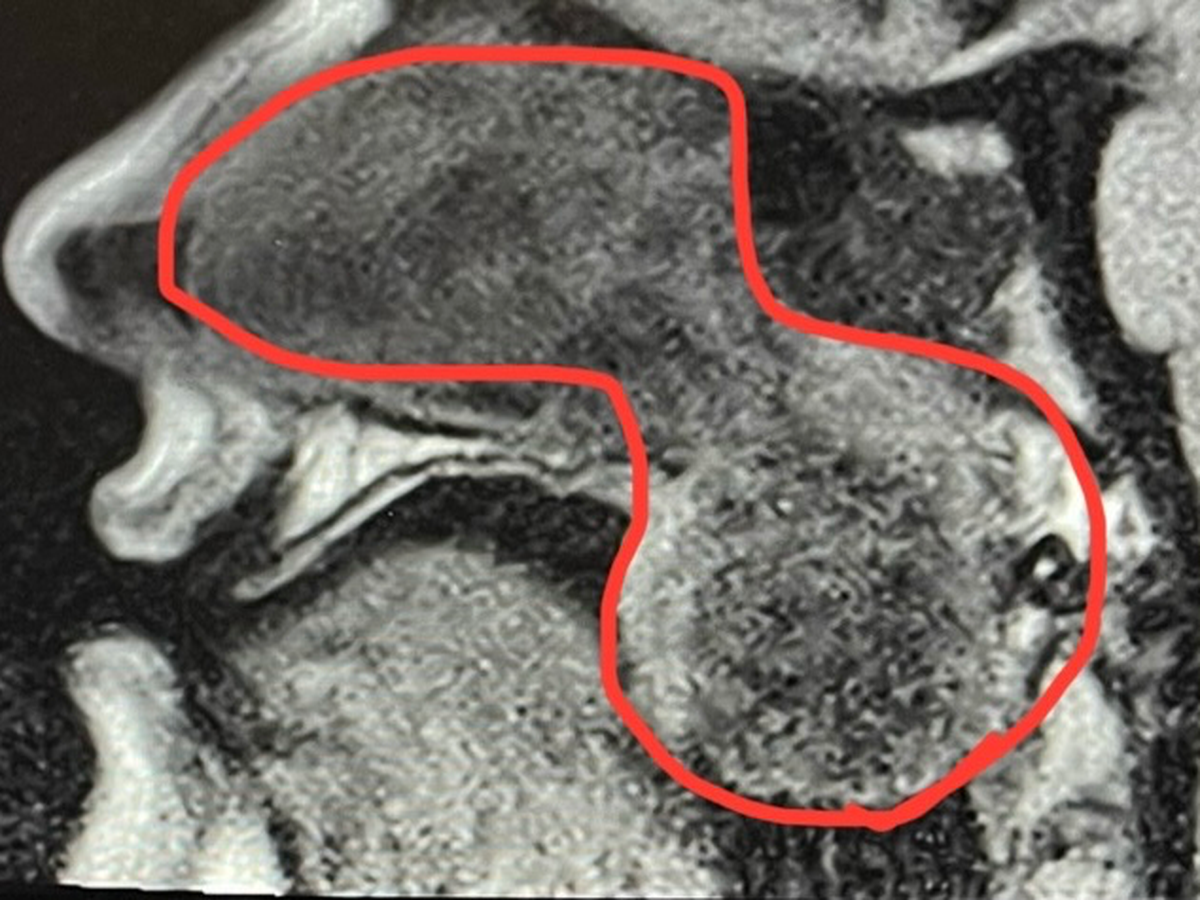

Alright, it's time for Round 2 of Sinus Surgery! Why didn't it work the first time, you may ask? Because the doctors I was with misdiagnosed me and made my problems WORSE! The nasal polyps I had came back in full force, and for the past few months, I've been going through tissue box after tissue box with the amount of mucus I seem to be producing. So now, not only can I not breathe out of my nose, but my nose is also always leaking! Not only that, but the polyps have gotten to the point where they're hanging in the back of my throat and impacting my breathing and speech. SO, all this to say, I need to get the surgery again so my new doctor can begin treating the root cause. Anything helps, whether it's a donation or just sharing this, but after my latest CT scan, my doctor is trying to get the surgery as soon as possible because of the effects it's having on my body.

TLDR: First doctors misdiagnosed me, so now I'm worse than before and have to do it all again. Also now, this doctor is in a hurry cause it's baaaaaad.